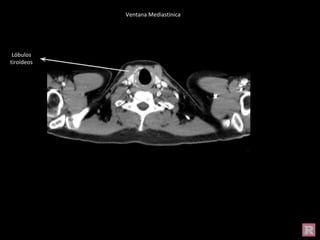

Ventana Mediastínica

Lóbulos

tiroideos

Cabeza humeral

Escápula

Costilla

Clavícula Ap. Transversa Lámina Ap. Espinosa Cuerpo

Vertebral

Pedículo

Vena Yugular

Interna

Carótida

Arteria

axilar